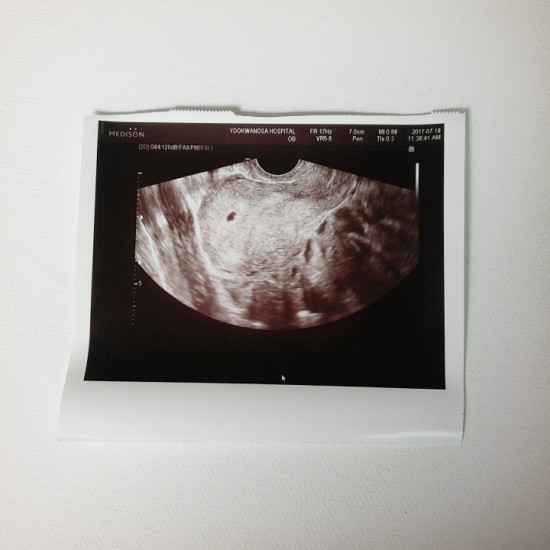

임신 17주 1일 2차 기형아 검사하러가면서 드디어 알게 된 우리 시봉이 성별 의젓하게 기다리고 싶었지만 ...

임신 17주~19주 3일